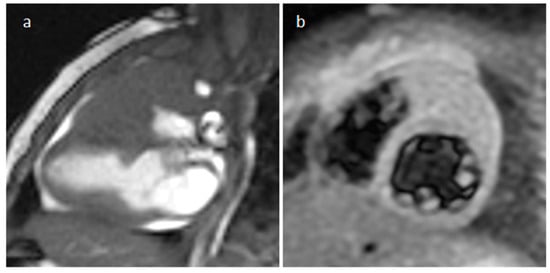

4.12. Paraganglioma

| Paraganglioma | Adulthood | On the roof of left atrium, right atrioventricular groove | elevated blood pressure and severe headaches | “salt and pepper” appearance, highly vascular, parasitizes blood supply from coronary arteries, elevated serum metanephrines Malignant up to 25% | Solid heterogeneous echogenic mass with clear boundaries, and detectable blood flow signals inside it in the color Doppler | A mass of soft-tissue density with homogeneous (smaller lesions) or peripheral (larger lesions with hemorrhage, necrosis and cystic degeneration) enhancement | Iso-hypo T1w, hyper T2w, peripheral LGE. Perfusion imaging shows strong enhancement |